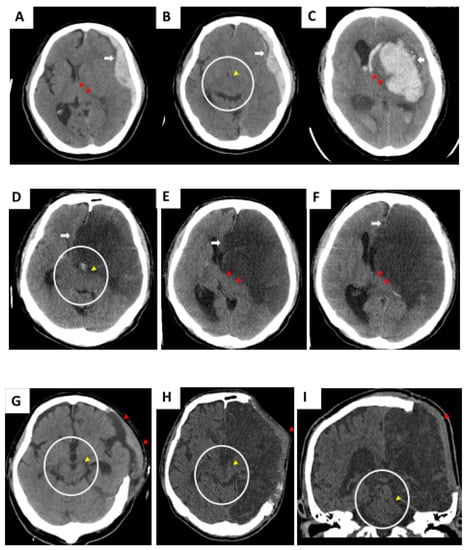

Representative pathological lesions of clinical cases 1–3 are highlighted in Figure 1A,B (TBI: acute subdural hematoma), Figure 1C (hemorrhagic stroke), and Figure 1D–F (malignant infarction-driven brain edema) respectively. Wide DC is beneficial to create additional volume for the injured brain to swell outward (indicated as a red triangle in Figure 1G (case 1), Figure 1H (case 3), and Figure 1I (case 3)) and, consequently, vacate a space for brainstem restoration through the removal of part of the skull bone together with the release of tension from the dura mater. After the DC procedure, the brainstem was morphologically restored, and the ambient cistern was opened widely (yellow arrow in circled area, Figure 1G (case 1), Figure 1H (case 3), and Figure 1I (case 3)).

Figure 1. Initial computed tomography (CT) scan showing compromised brainstem due to acute subdural hematoma (SDH) (A,B, case 1), hemorrhagic stroke (C, case 2), and malignant cerebral infarction (DF, case 3). Alteration of brainstem shape was caused by intracranial mass effect. Wide decompressive craniectomy (DC) should be performed immediately to create extensive volume, which accommodates postoperative brain swelling. (GI) Brainstem shape was morphologically regained.